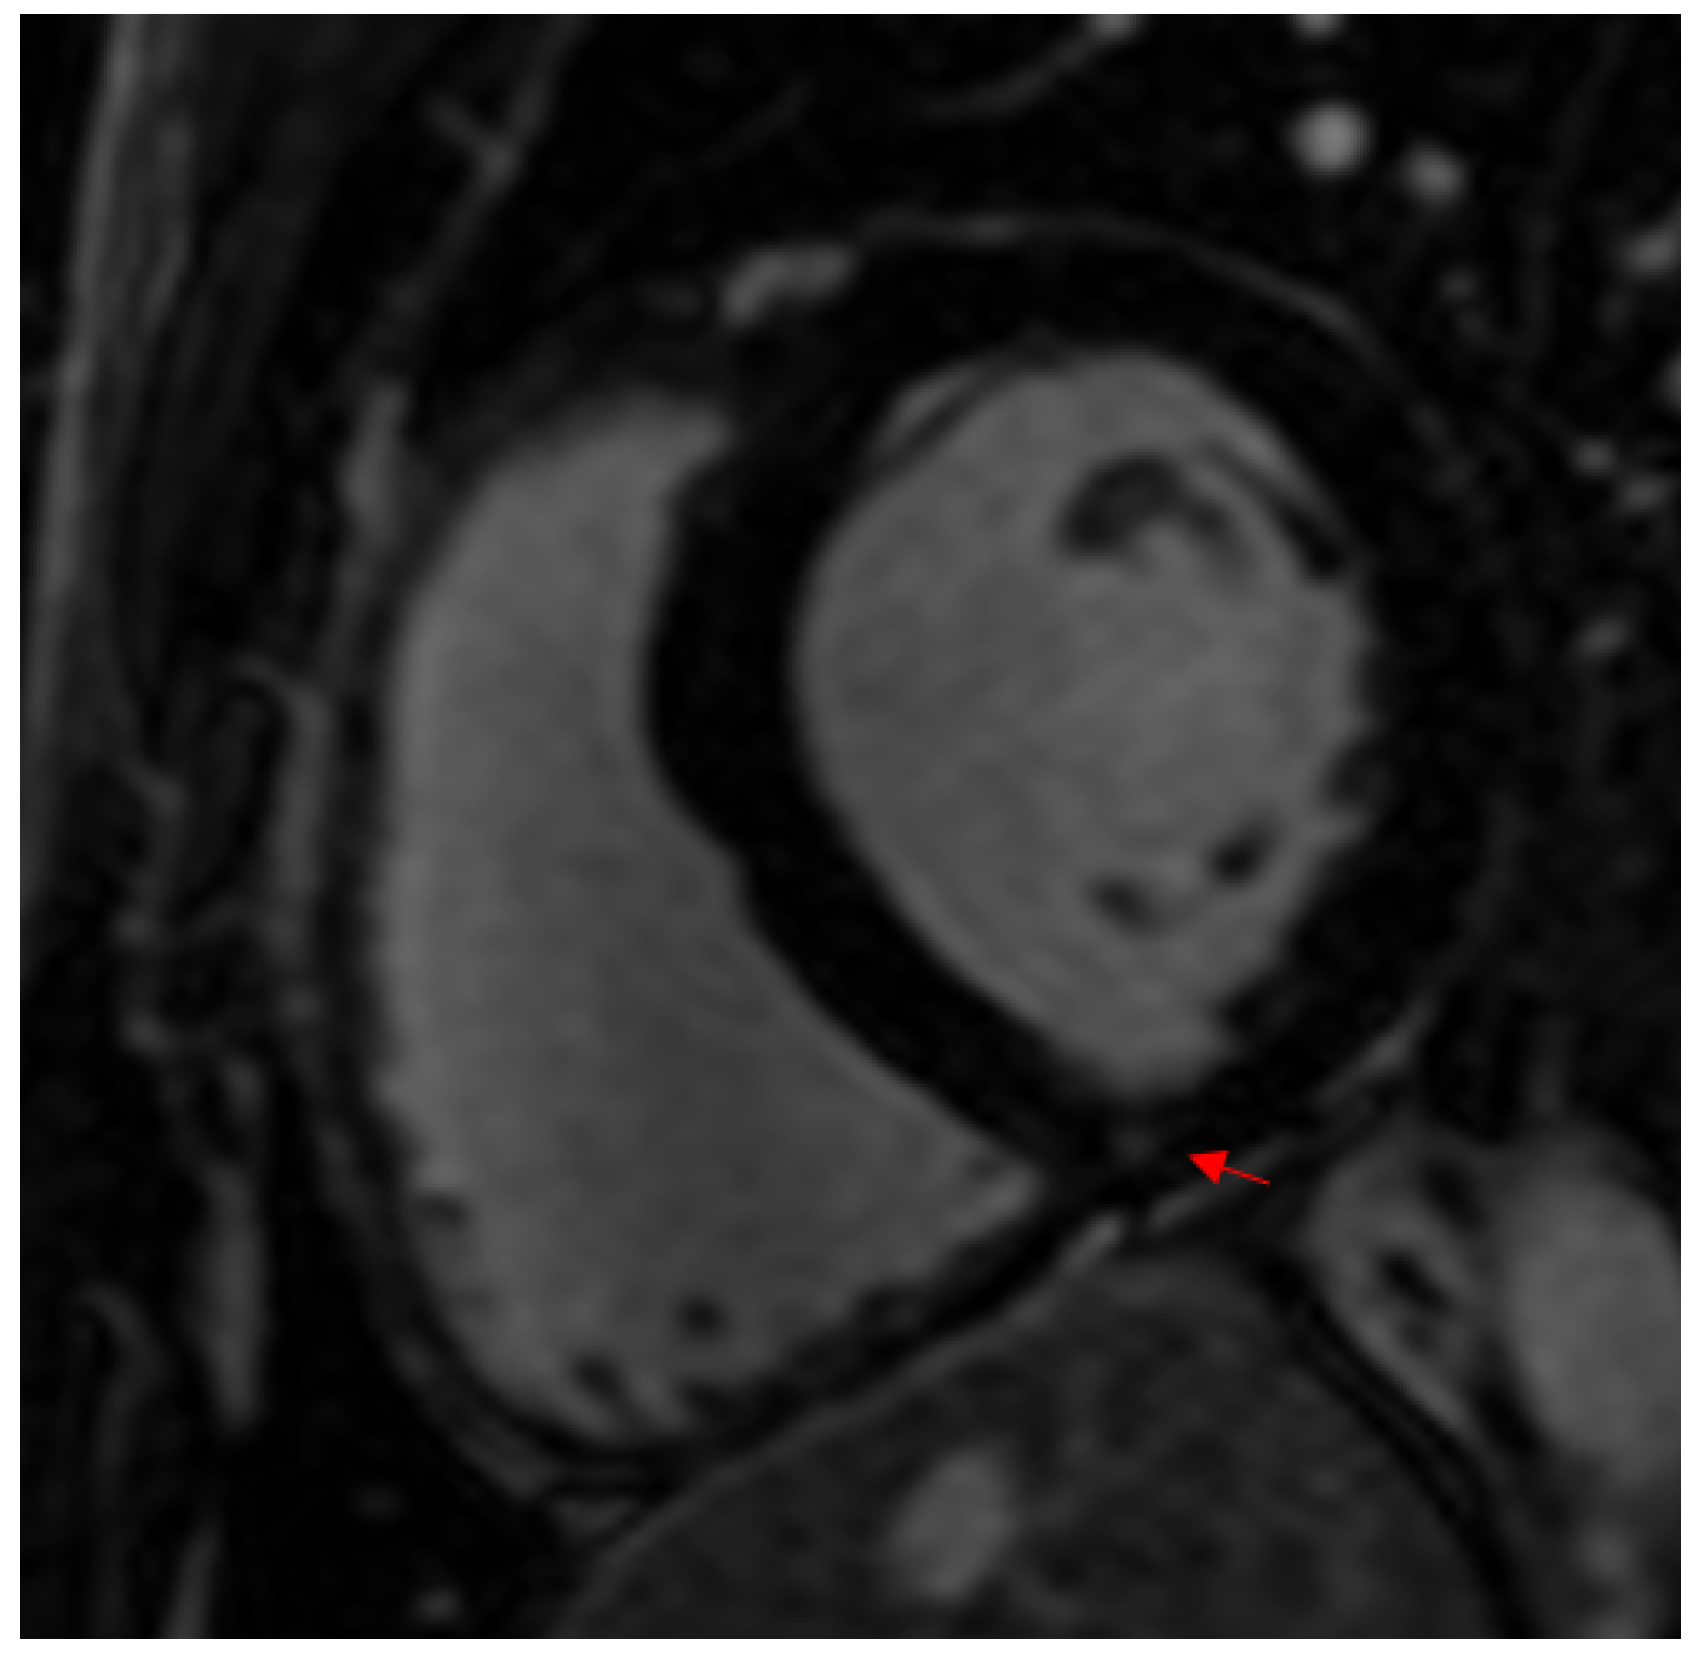

4. Discussion

4.1. Myocardial Fibrosis in Athletes and the General Population

4.2. Factors Associated with Myocardial Fibrosis in Athletes

4.2.3. Viral Myocarditis

- Crescenzi, C.; Zorzi, A.; Vessella, T.; Martino, A.; Panattoni, G.; Cipriani, A.; De Lazzari, M.; Marra, M.P.; Fusco, A.; Sciarra, L.; et al. Predictors of Left Ventricular Scar Using Cardiac Magnetic Resonance in Athletes with Apparently Idiopathic Ventricular Arrhythmias. J. Am. Heart Assoc. 2021, 10, e018206. [Google Scholar] [CrossRef] [PubMed]

- Zorzi, A.; Marra, M.P.; Rigato, I.; De Lazzari, M.; Susana, A.; Niero, A.; Pilichou, K.; Migliore, F.; Rizzo, S.; Giorgi, B.; et al. Nonischemic Left Ventricular Scar as a Substrate of Life-Threatening Ventricular Arrhythmias and Sudden Cardiac Death in Competitive Athletes. Circ. Arrhythmia Electrophysiol. 2016, 9, e004229. [Google Scholar] [CrossRef]

- Schnell, F.; Claessen, G.; La Gerche, A.; Bogaert, J.; Lentz, P.-A.; Claus, P.; Mabo, P.; Carré, F.; Heidbuchel, H. Subepicardial delayed gadolinium enhancement in asymptomatic athletes: Let sleeping dogs lie? Br. J. Sports Med. 2016, 50, 111–117. [Google Scholar] [CrossRef]